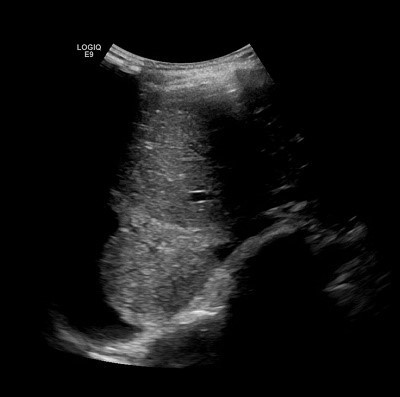

در سونوگرافی ریه از پروب های مختلف بسته به نیاز استفاده می شود. معمولا از پروب خطی با فرکانس بالا برای بررسی نواحی نواحی سطحی مانند پلور ، و از پروب کانکس یا میکروکانکس با فرکانس پایین تر برای ارزیابی ساختار های عمقی تر استفاده می گردد. به دلیل اینکه هوا در ریه ها باعث بازتاب امواج صوتی می شوند ، تصاویر مستقیم از پارانشیم ریه در حالت طبیعی بدست نمی آید. اما حضور مایعات ، ضخامت پلور یا تغییرات غیر طبیعی در بافت ، الگوهای خاص ایجاد میکند که در سونوگرافی به وضوح قابل شناسایی هستند.

الگوهای سونوگرافی ریه چیست؟

خطوط A : خطوط موازی و افقی با پلور ، نشان دهنده ی تهویه طبیعی ریه است.

خطوط B : خطوط عمودی که از پلور منشا می گیرد و تا عمق تصویر ادامه می یابند ، نشان دهنده وجود مایعات در فضای بینابینی ریه است  ، مانند ادم ریوی.

کنسولیداسیون : مناطقی از ریه که پر از مایع و یا سلول شده اند و امواج صوتی را عبور می دهند ، مانند آبسه ریه.

پلورال افیوژن : حضور مایع در فضای پلور که به صورت لایه های بدون پژواک مشاهده می شود.

پنوموتوراکس : در این حالت حرکت لغزشی پلور از بین میرود و علامت خط سکوت ممکن است مشاهده شود.